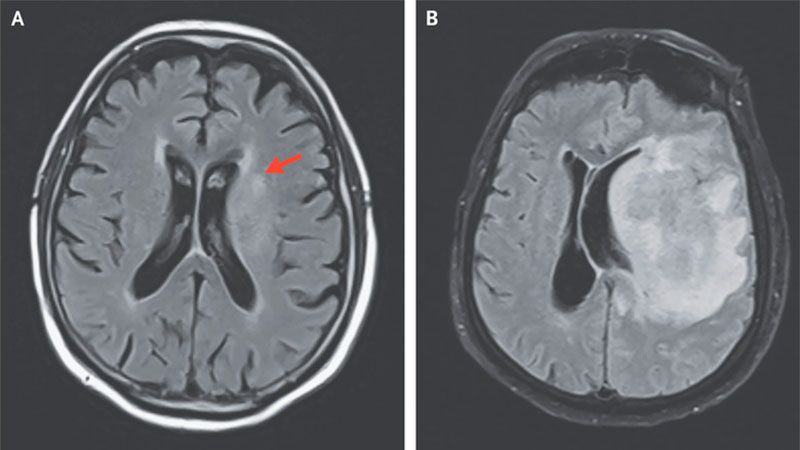

Una autopsia realizada al anciano reveló necrosis por licuefacción del cerebro y se realizó el diagnóstico de encefalitis amebiana granulomatosa. Esta condición se caracteriza por la disolución parcial o completa del tejido muerto, en este caso del cerebro, y la transformación en una masa líquida y viscosa, recoge The Science Times.